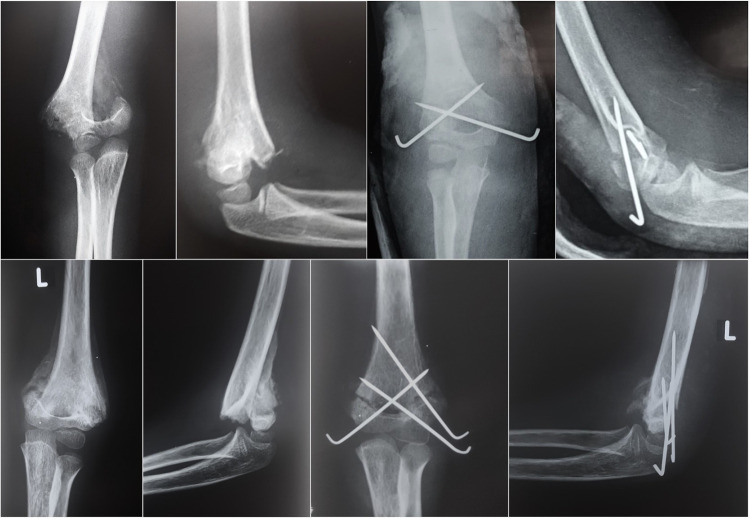

Background: Supracondylar humeral fracture (SCHF) is a common injury in children, and early treatment provides excellent results and prevents disabilities. Delayed presentation is still prevalent, mainly in developing countries, because many factors hinder the opportunity to receive appropriate treatment. Currently, there are no standard treatment protocols, and there is insufficient published literature on this topic. This study aimed to evaluate the effectiveness and outcomes of open reduction and Kirschner wire fixation using a triceps-sparing posterior approach in neglected cases with complicated fractures.

Methods: This was a prospective multicenter clinical study conducted between July 2016 and June 2021, which included 28 pediatric patients with neglected SCHF who presented to the hospital for definitive treatment five days or more after initial trauma without previous surgical intervention. All the patients underwent open reduction and K-wire fixation using a posterior triceps-sparing approach. The final functional outcome was assessed using the Mayo Elbow Performance Index (MEPI) and Flynn criteria.

Results: All fractures (100%) united within 3-5.5 weeks (mean 4 ± 0.7 weeks). Excellent scores observed in 67.9% (n = 19), good in 21.4% (n = 6), fair in 7.1% (n=2), and poor in 3.6% (n = 1) patients according to MEPI. Correspondingly, Flynn's criteria showed 96.4% (n = 27) satisfactory and 3.6% (n = 1) unsatisfactory outcome.

Conclusion: Open reduction and fixation using Kirschner wires through the posterior triceps-sparing approach is an effective treatment method for late-presenting SCHF in children with consequent satisfactory results.